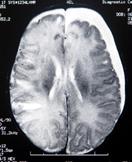

Ликворо-краниальный (ЛКИ) индекс представляет процентное отношение объема ликворных пространств ребенка к объему полости черепа. Методика измерения ликворо-краниального индекса наиболее точно отражает основные внутричерепные взаимоотношения и состояние ликворных пространств.

Объем мозга составляет разницу между объемом краниальной полости и объемом ликвора. У детей в норме ЛКИ составляет 2-3%, на седьмом десятилетии жизни в связи с процессами атрофии достигает 10-15%.